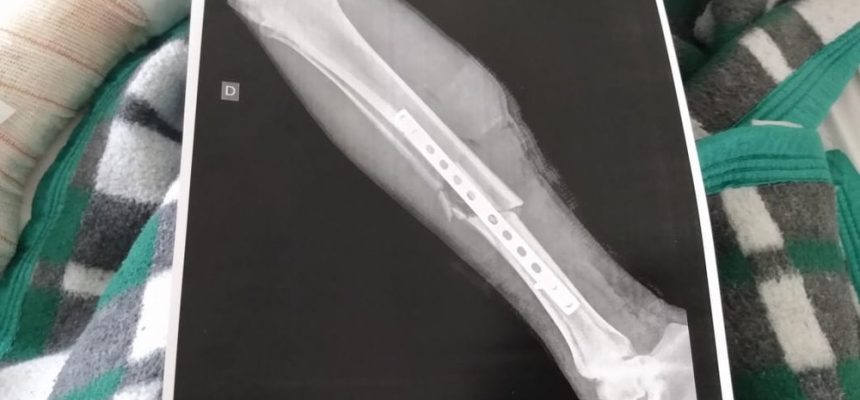

Em 01/10/2019O homem que foi atropelado por uma viatura da Polícia Militar durante uma ocorrência em Araçariguama (SP) continua internado após passar por cirurgia. Uma nova avaliação nesta segunda-feira (30) vai definir se ele passará por outro procedimento. O exame de raio X mostra as fraturas que o morador teve em uma das pernas depois de ser atropelado... Leia mais

Em 30/09/2019Um vídeo gravado pro uma moradora mostra quando uma viatura da Polícia Militar atropela um homem em Araçariguama (SP), na madrugada deste sábado. Nas imagens, é possível ver uma discussão entre a equipe e alguns jovens que estavam no local. Eles reclamam que os policiais usaram gás lacrimogênio durante a abordagem. Em seguida, os policiais... Leia mais